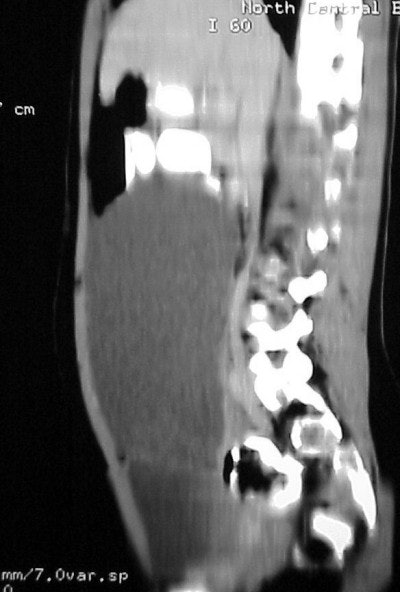

The images (Figures TC 5 and TC 6) show, respectively, a sagittal and coronal MPR of the axial images, demonstrating the size and volume of the structure.